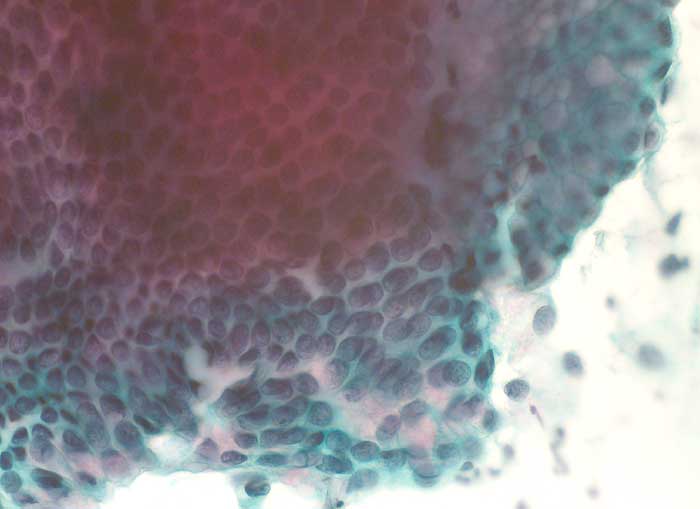

PathoPic – image database / PathoPic ID 6217 - normale endozervikale Zylinderepithelien

normale endozervikale Zylinderepithelien

Portioabstrich: Normale endozervikale Zylinderzellen von seitlich aufgenommen mit intrazytoplasmatischer Schleimbildung und basalständigen hellen rundlichen Kernen. Von oben betrachtet sind die Zylinderzellen in regelmässigen Abständen angeordnet und die Zellgrenzen bilden ein Honigwabenmuster.

Zytologie

400